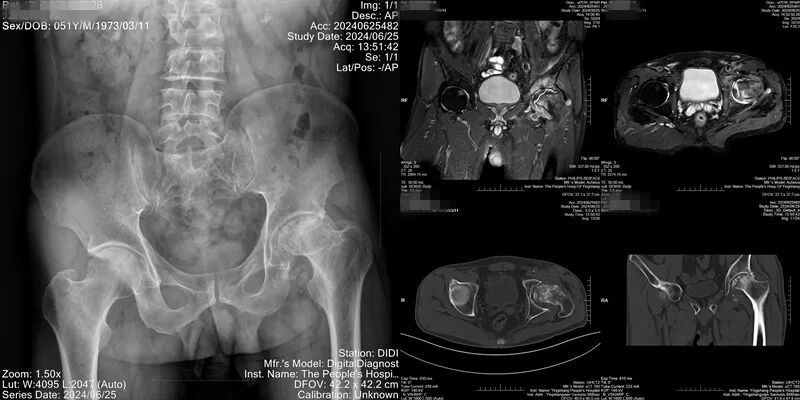

患者有长期大量饮酒史,左髋关节疼痛已经3年多,此次慕名前来。李明全对患者查体及髋关节磁共振提示患者双侧股骨头无菌性坏死,X线检查提示右侧股骨头形态无明显异常,左侧股骨头变性、塌陷,头下囊性变,左髋关节间隙变窄,髋臼骨质增生,按照股骨头坏死ARCO分期,右侧为ARCOII期(建议保守治疗),左侧为ARCOIV期(建议手术治疗)。